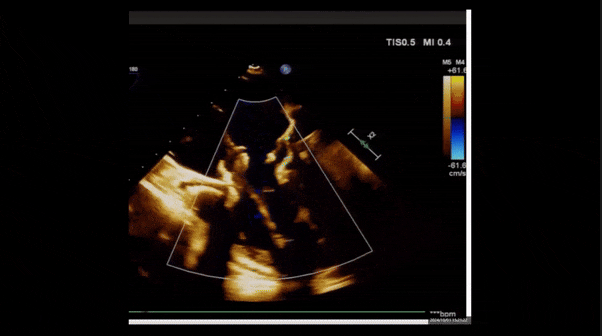

術(shù)后即刻返流

術(shù)后三維超聲

術(shù)后即刻經(jīng)食道超聲可見,三尖瓣假體瓣膜位置合適,牛心包瓣葉運動狀態(tài)良好,開閉正常,瓣周及瓣葉對合緣處未見明顯返流,心電圖及心包狀態(tài)較術(shù)前無明顯變化。